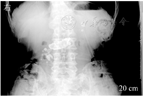

CP典型的CT表现为胰腺钙化、胰管扩张、胰腺萎缩,其诊断的灵敏度和特异度分别为80%、90%以上[24]。CT检查是显示胰腺钙化的最优方法(图2),CT平扫检查可显示胰腺微小钙化灶。常规MRI检查对CP的诊断价值与CT相似,对胰腺实质改变检查敏感,但对钙化和结石的显示不如CT。MRCP主要用于检查胆、胰管的病变,如主胰管扩张、胰腺先天变异、胆管扩张或狭窄等(图3)。

| 影像学特征性表现 | 下列任何一项:①胰管结石;②分布于整个胰腺的多发钙化;③ ERCP显示主胰管不规则扩张和全胰腺散在不同程度的分支胰管不规则扩张;④ ERCP显示主胰管完全或部分梗阻(胰管结石或蛋白栓),伴上游主胰管和分支胰管不规则扩张 | 下列任何一项:① MRCP显示主胰管不规则扩张和全胰散在不同程度的分支胰管不规则扩张;② ERCP显示全胰腺散在不同程度分支胰管扩张,或单纯主胰管不规则扩张,或存在蛋白栓;③ CT检查示主胰管全程不规则扩张伴胰腺形态不规则改变;④超声或超声内镜显示胰腺内高回声病变(考虑结石或蛋白栓),或胰管不规则扩张伴胰腺形态不规则改变 |